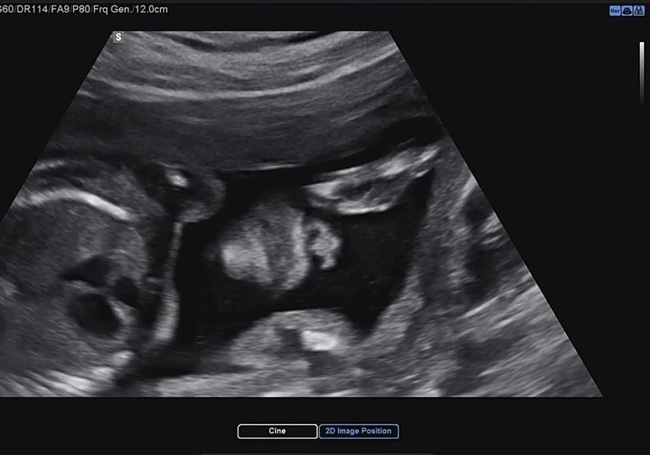

임신일기_25~28주, 입체초음파